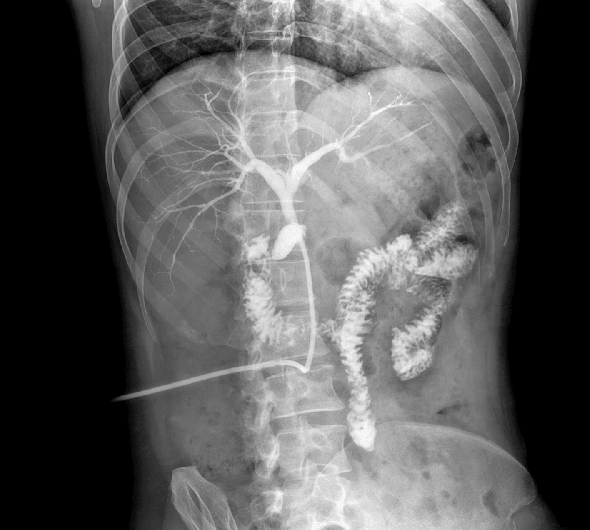

臨床圖像